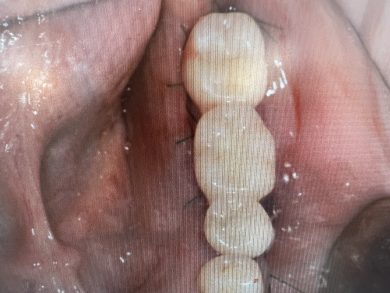

執刀したのは、勤務医のM先生。彼にとって、昨日は人生で初めてのインプラント埋入手術でした。ガイドサージェリー全盛ですが、かれはフリーハンドで完璧にオペしました。

左下に2本。最遠心にはテンポラリーインプラントを入れて、患者さんは手術当日から咬めるようになりました。

昨日のM先生のオペには、あのS先生が持っていた「センス」と、それ以上に裏打ちされた「丁寧な準備の跡」が重なって見えました。初めてのオペとは思えないほどスムーズな手際、組織への愛護的な扱い、そして理想的な位置への埋入。